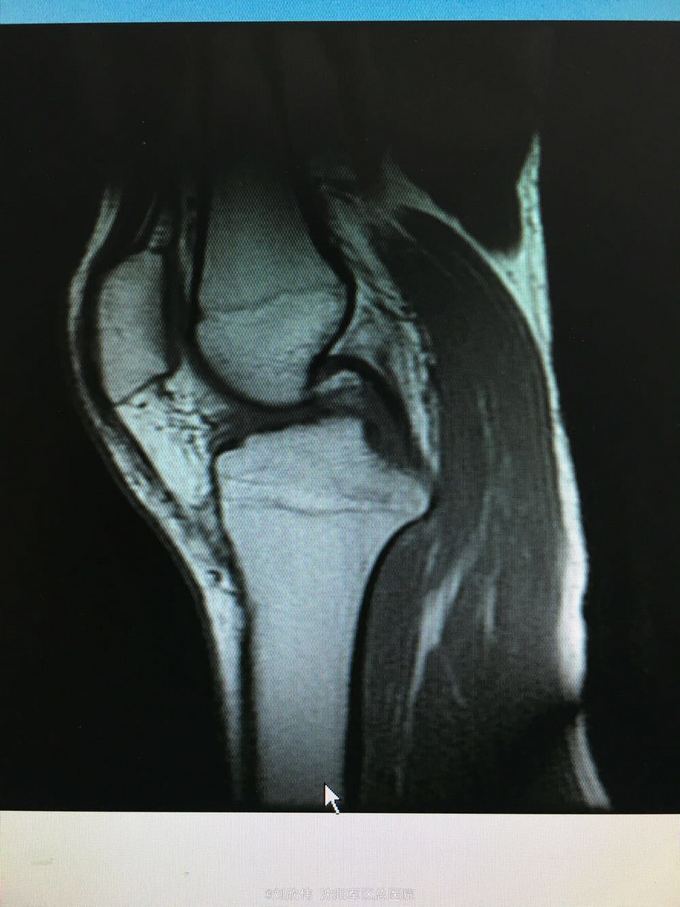

训练致右膝肿痛伴活动受限3个月 自觉脱臼感

右膝lachman试验,轴移试验阳性 MRI提示ACL已显示不清,半月板后角高信号(但术中未见撕裂,mri存在假阳性)

右膝前交叉韧带断裂 右膝半月板损伤 手术方法如题,直接上图